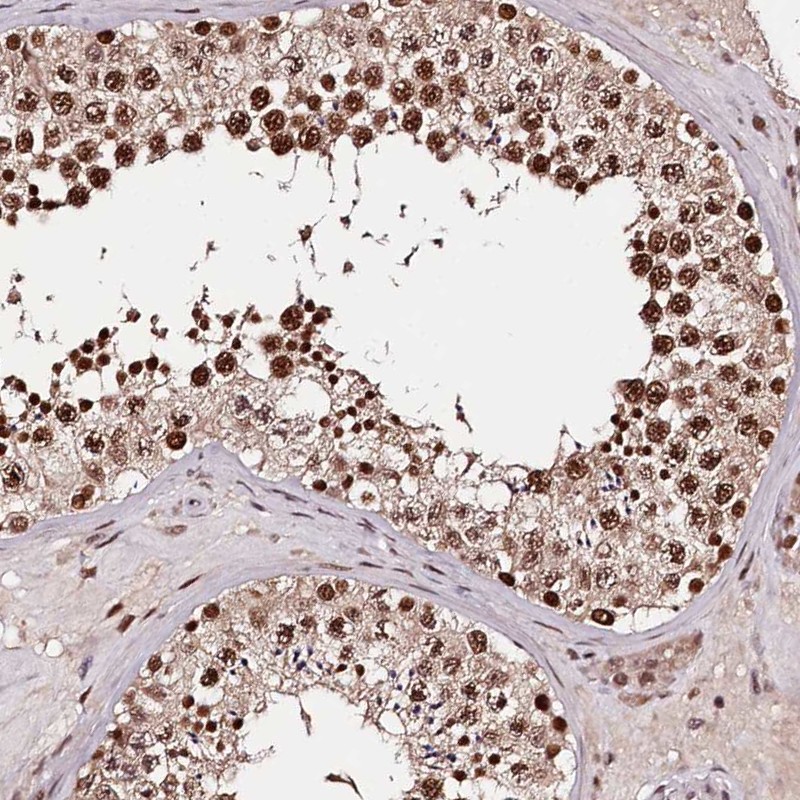

Immunohistochemical staining of human testis shows strong nuclear positivity in cells in seminiferous ducts.